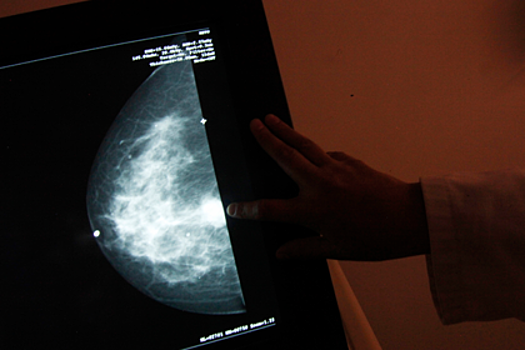

Рак молочной железы является второй ведущей причиной смерти женщин в Австралии. Только в 2018 году в стране было обнаружено 18 тысяч новых случаев заболевания.